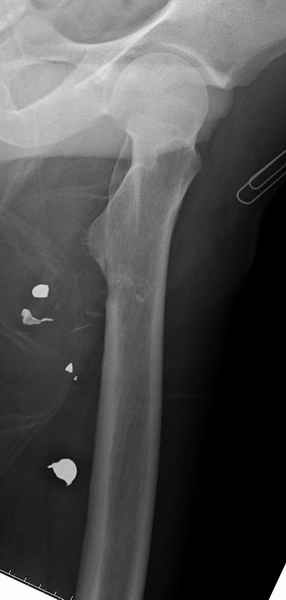

Больной с огнестрельным переломом бедра с вовлечением около 15% медиального кортекса, входное отверстие около 1 см в диаметре; стабильный, без сосудистых и неврологических признаков.

Входные маленькие отверстия от ранении просто игнорируются, никаких дренажей, как любое колотое ранения, они закрываются и были случаи через месяц. Конечно, ведется профилактика открытых ранении: сыворотки и т.д., но еще самое главное уделяем профилактике образования перелома из-за стресса в результате дефекта кортикального слоя.

Литературные данные о влиянии кортикального дефекта на стрессовые переломы в длинных трубчатых костях в основном встречаются в онкологии, например кортикальный дефект более 50% имеет больше шанса стрессовых переломов, чем в нашем случае.

Учитывая, что больной получил травму не во время визита в церковь, и он является одним из представителем 40 миллионного “outstanding itizen”, без медицинской страховки, без работы в свои 39 лет, и без надлежающей ортопедической дисциплины у которого отсутсвует страх стрессового перелома, было рекомендовано оперативное лечение: профилактическое антеградное интрамедуллярное штифтование.

Методика штифтования при отсутствии большой зоны перелома как при онкологических профилактических штифтованиях, расверливание интрамедуллярного канала проводим с предварительным наложением дополнительного дренажного отверстия в дистальном отделе бедра (в данном случаи в канале оставили 6.5 мм канюлированный шуруп), иначе при создании давления в канале во время сверления имеется опасность эмболизации легочной артерии тромбом.